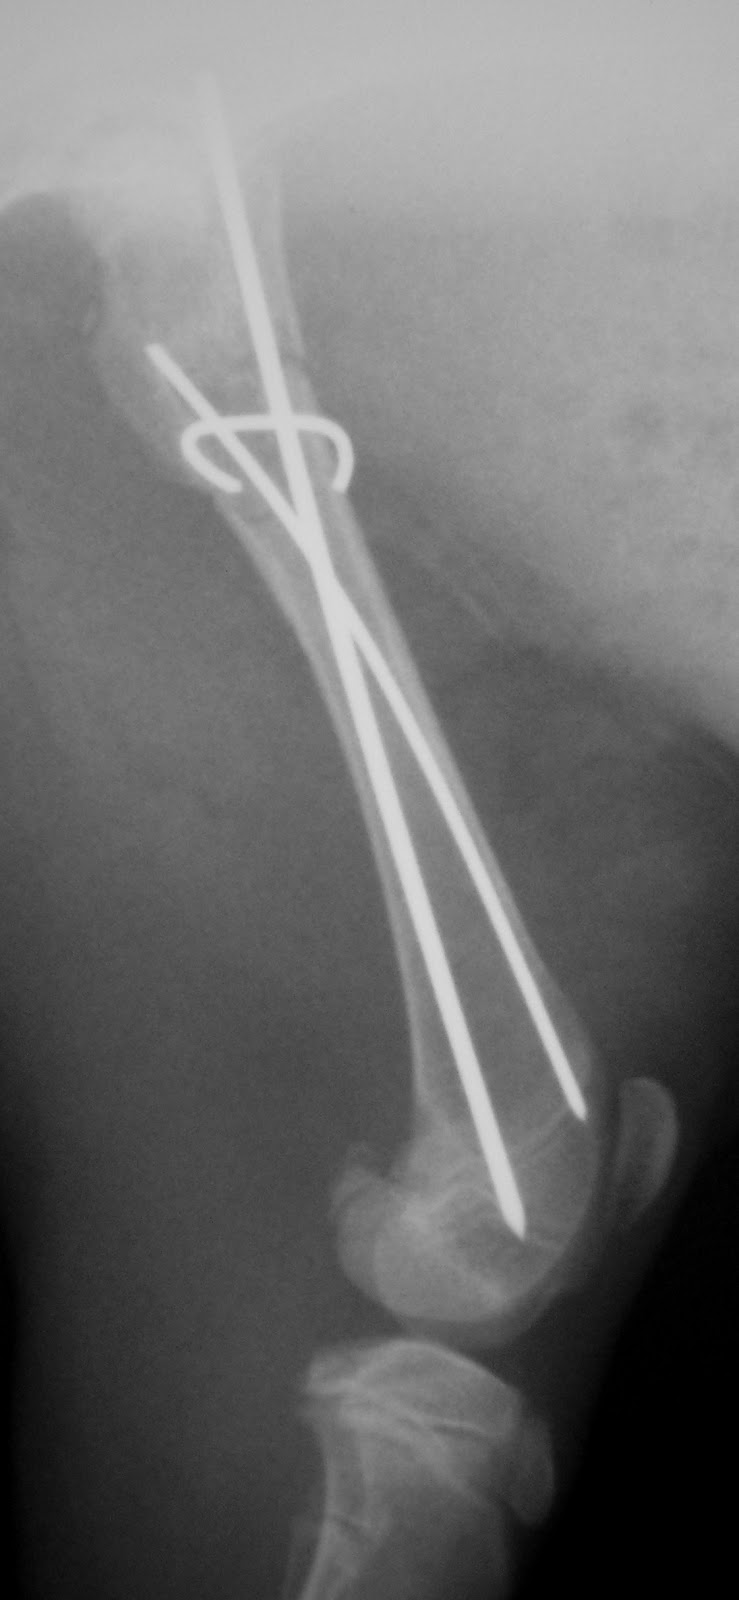

| Οστεοσύνθεση με ήλους |

| Πέρας επέμβασης α΄ |

| Πέρας επέμβασης β΄ |

| Πέρας επέμβασης γ |